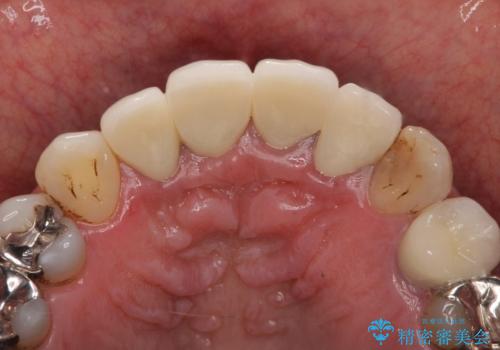

老朽化した前歯のクラウンやりかえ

X線写真より問題のなかった根管治療は行わず、クラウンを除去し仮歯でを装着したのちジルコニアクラウンを製作していきます。

- 48.4万円(税込)(仮歯・ジルコニアクラウン×4)費用は治療当時の料金となります